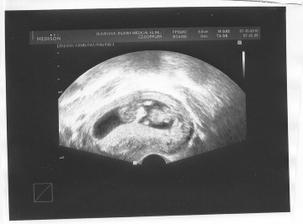

7.10. 11+2tt třetí kontrola. Kobliha má 3,8mm, stále vše ok. Krev na nt screening